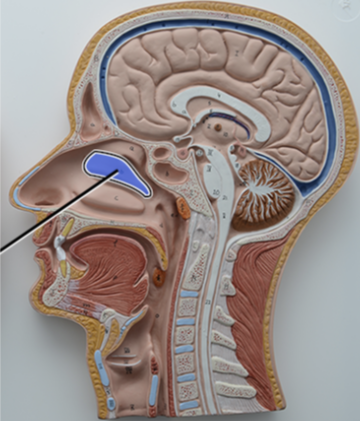

What structure is this?

Diaphragm

What structure is this?

Hard Palate

What structure is this?

Soft Palate

What structure is this?

Uvula

What structure is this?

Nasal cavity

What structure is this?

Superior Nasal Concha

What structure is this?

Middle Nasal Concha

What structure is this?

Inferior Nasal Concha

What structure is this?

The nasopharynx region of the pharynx

What structure is this?

The Oropharynx region of the pharynx

What structure is this?

The Laryngopharynx region of the pharynx

Nasal Septum